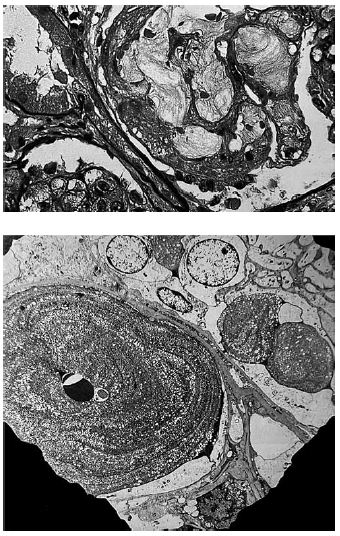

Paciente do sexo masculino, 40 anos de idade, asiático, apresenta hematúria, proteinúria e síndrome nefrótica resistente à corticoterapia. O anatomopatológico está representado nas figuras a seguir.

O provável diagnóstico é